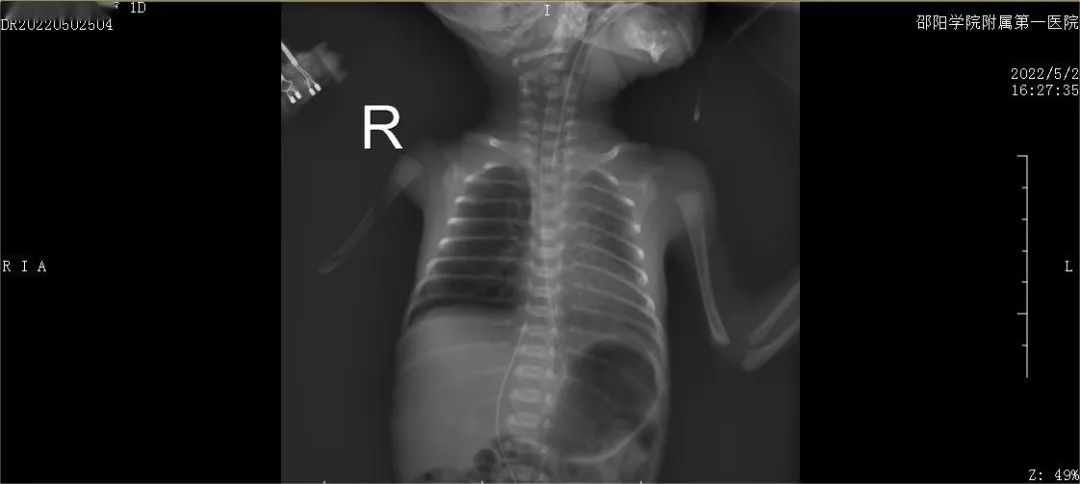

胸片检查:生后6小时(第一次PS后):双肺纹理稍增粗,双肺透亮度稍减低,双肺野可见散在斑片状模糊影。上腹部可见UVC管影,尖端位于T8/9椎间隙水平;生后24小时(第二次PS后):双肺纹理增多、增粗,模糊,右肺透亮度稍减低。与老片对比,透亮度较前增高。第21天:双肺纹理增多,双肺透亮度稍减低,双肺可见多发小斑片状模糊影,右上肺野可见片状致密影。心脏超声:第4天:心脏彩超:卵圆孔未闭、动脉导管未闭(PDA,3.5mm)。第8天:心脏彩超:卵圆孔未闭、动脉导管未闭(1.7mm)。第13天:心脏彩超:卵圆孔未闭,三尖瓣轻度返流。头颅B超:2次颅内超声未见明显异常声像。头颅磁共振平扫(MRI)(生后50天):符合早产儿脑改变。听性脑干及耳声发射双侧通过。小儿广域眼底摄像:双眼视网膜血管未完全化。

生后24小时(第二剂PS后)